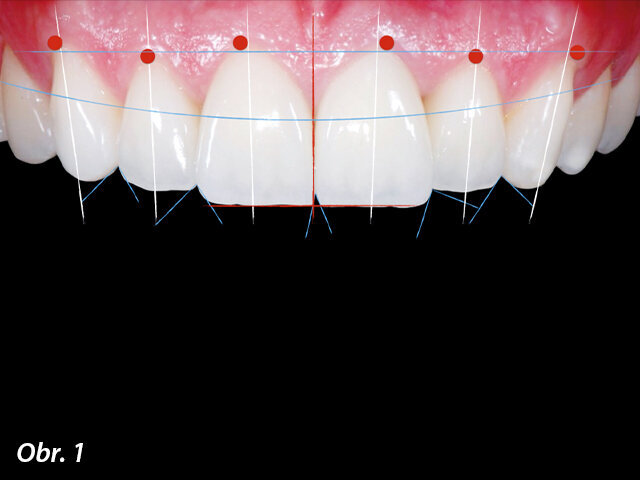

Po externí resorpci kořene měla mladá 28letá pacientka nenávratně poškozen zub 11. Byla zjištěna vestibulární píštěl a sekvence rentgenových snímků vykazovala progresivní poškození kořene, které zahrnovalo střední a cervikální třetinu kořene zubu (obr. 2–5).